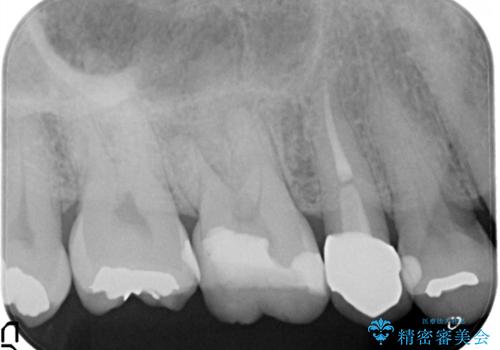

- 定期検診にて、奥歯の頬側歯肉にサイナストラクトが発見された患者様です。

根管治療から歯冠修復まで行っております。

サイナストラクト(瘻孔)から原因歯を特定し治療を行っております。根管治療を行った歯牙は破折リスクが高くなるため被せものによる治療を提案しております。